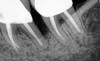

The consensus report from the AAP's work-shop group on intrabony defects presents evidence that periodontal regeneration in intrabony defects is possible on previously diseased root surfaces, demonstrated by gains in clinical attachments, reductions in periodontal pocket depths, gains in radiographic bone heights, and overall improvements in periodontal health.9 These clinical findings are consistent with available histologic evidence, and the clinical improvements can be maintained over long periods of time (ie, > 10 years).9 Although bone replacement grafts have been a commonly investigated modality, guided tissue regeneration, biologics, and combination therapies have also been shown to be effective. Early management offers the greatest potential for successful periodontal regeneration.9 Figure 9 through Figure 11 depict the treatment of a tooth with probing depths of equal to or greater than 15 mm using mineralized FDBA.

(9.) Pretreatment radiograph of tooth with probing depths of equal to or greater than 15 mm.

Figure 9